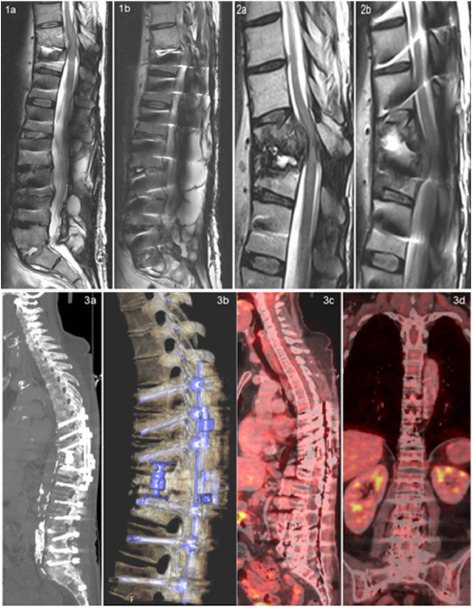

FDG PETCT in April 2025 3a 3d shows extensive spinal instrumentation without a residual FDG avid inflammatory focus in the spine or paravertebral tissues